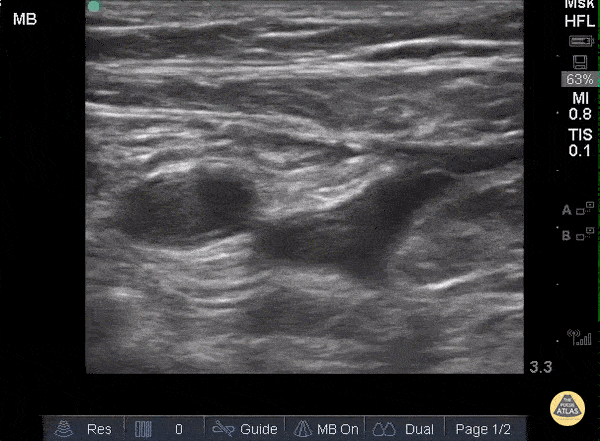

When applying pressure to the ultrasound probe, veins collapse first while arteries remain patent and pulsatile. In this clip one can see that proximally, the large pulsatile vessel (which represents the common femoral artery) sits adjacent to a mostly compressible common femoral vein. As the probe moves distally and both the artery and vein split into deep and superficial branches, the superficial femoral vein is not entirely compressible along its medial aspect, representing a thrombus. Sukh Singh, MD